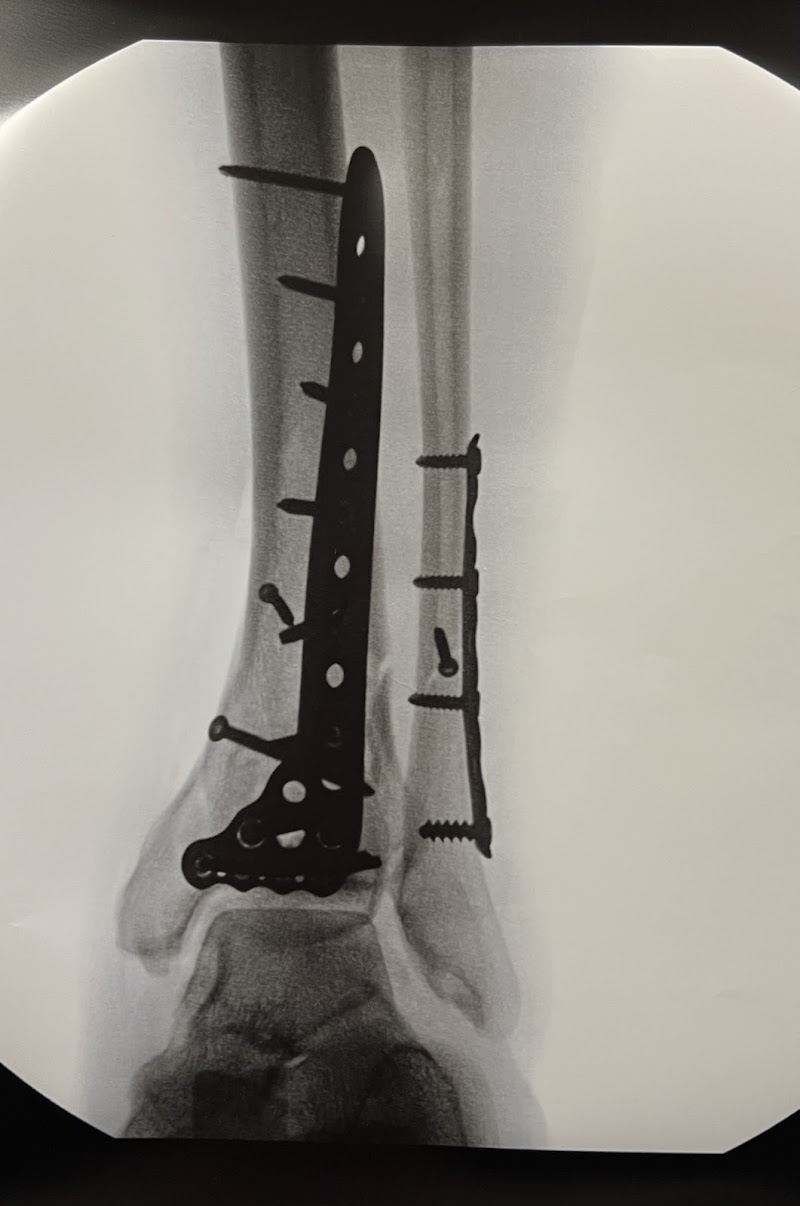

Whether the issue is a recent sports injury or years of joint wear, orthopedic specialists take a methodical approach to diagnosis and treatment. Joint replacement consultations, fracture care, and sports medicine services are among the specialties covered here.